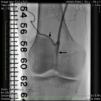

Case reportA 50-year-old Caucasian woman with hypertension, tobacco abuse, and peripheral arterial disease with life-limiting claudication had stents placed in bilateral 80% ostial iliac artery lesions two months previously. She was also noted to have a CTO of the left SFA at the ostium with no obvious stump (Figure 1) which was reconstituting distally via collaterals just above the popliteal artery (Figures 2 and 3). Due to her ongoing symptoms despite optimal medical therapy, it was decided to intervene on the SFA. Since there was no obvious stump of the occluded SFA proximally, we decided to approach the CTO through a retrograde approach.